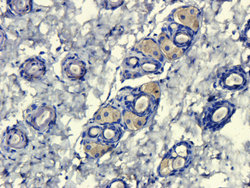

- Submitted by

- antibodies-online (provider)

- Main image

- Experimental details

- IHC